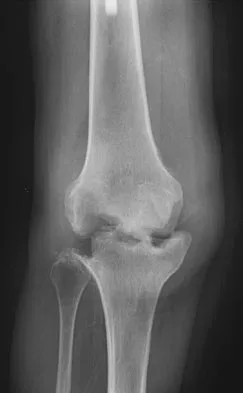

A 52-year-old man who was a former high school pitcher now reports loss of elbow flexion and extension with pain at the extremes of motion. Nonsurgical management has failed to provide relief. Examination reveals movement from 50 degrees to 110 degrees and is painful only at the limits of motion. A radiograph is shown in Figure 12. Treatment should consist of

Explanation

Based on the history, examination, and radiograph, the patient has typical degenerative arthritis of the elbow. This condition is found almost exclusively in men, and there is almost universally a history of repetitive heavy use or overuse of the elbow. Patients report pain at terminal extension and usually have a flexion contracture. Radiographs reveal osteophytes on the coronoid and olecranon and in the coronoid and olecranon fossae. The osteophytes are often associated with loose bodies that sometimes are attached to the soft tissues. Treatment should consist of removal of all loose bodies and impinging osteophytes using open technique or by arthroscopy. The capsular contractures should be released at the same time. Kasser JR (ed): Orthopaedic Knowledge Update 5. Rosemont, IL, American Academy of Orthopaedic Surgeons, 1996, pp 283-294. Morrey BF: Primary degenerative arthritis of the elbow: Treatment by ulnohumeral arthroplasty. J Bone Joint Surg Br 1992;74:409-413. Redden JF, Stanley D: Arthroscopic fenestration of the olecranon fossa in the treatment of osteoarthritis of the elbow. Arthroscopy 1993;9:14-16.